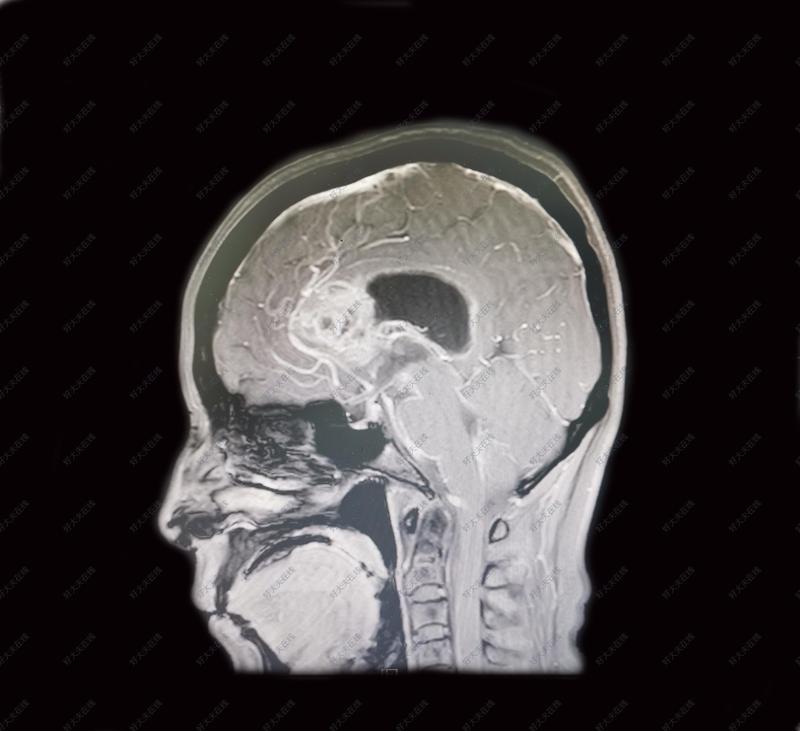

双侧胼胝体体部胶质瘤_胶质瘤 - 好大夫在线

图片尺寸691x800